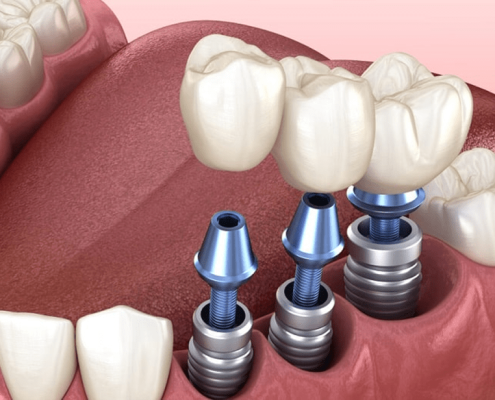

ایمپلنت به روش پانچ یا ایمپلنت بدون درد چیست؟

آیا میدانید داشتن لبخند زیبا با دندان های یکدست حتی در سنین پیری تا چه اندازه بر زیبایی چهره تاثیرگذار خواهد بود؟ به نظر شما بهترین راه برای جایگزین دندانهای از دست رفته چه روشی است؟ آیا تا به حال نام ایمپلنت فوری یا ایمپلنت پانچ را شنیدهاید؟ همان طور که میدانید همه ما در طول زندگی ممکن است بر اثر عوامل گوناگونی چون کهولت سن، تصادف، زمین خوردن، عفونت لثه و ... یک یا چند دندان خود را از دست بدهیم. از آنجایی که دندان تاثیر بسزایی بر زیبایی طرح لبخند و به تبع چهره خواهد داشت، بنابراین هیچ فردی علاقه ندارد حتی یک روز را بدون دندان سپری کند. از این رو در حوزه دندانپزشکی زیبایی شیوههای متفاوتی برای پر کردن جای خالی دندانها وجود دارند که یکی از آنها کاشت دندان به روش ایمپلنت پانچ یا ایمپلنت بدون درد است که در ادامه بیشتر با آن آشنا خواهید شد.

ایمپلنت کامل دهان یا فول موس

داشتن دندانهایی صاف و یکدست را میتوان یکی از موهبتهای الهی دانست. با گذشت زمان به علت کهولت سن، اتفاقات نامترقبه و هر علت دیگری امکان دارد که دندانها از بین بروند. در این شرایط تصور بسیاری از افراد بر این است که دندانهای خود را برای همیشه از دست دادهاند و تنها راه چاره استفاده از دندان مصنوعی است. در حالی که با پیشرفت علم و تکنولوژی، شما میتوانید از جایگزینی مشابه دندانهای خود استفاده کنید. ایمپلنت کامل دهان امروزه یکی از روشهای رایج درمانی به حساب میآید که به کمک آن شما میتوانید فضای خالی همه دندانهای از دست رفته خود را پر کنید. با انجام ایمپلنت کامل دهان یا فول موس شما همچون روز اول، دندانهایی صاف و یکدست خواهید داشت.